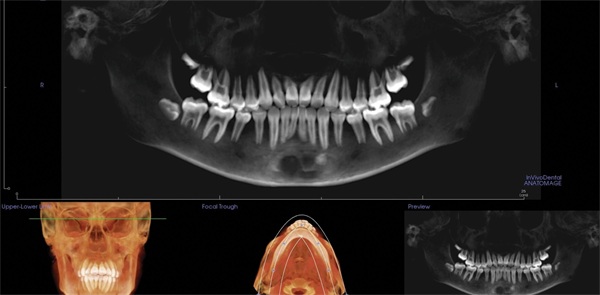

The final panoramic radiograph showed acceptable root positioning with no obvious radiographic evidence of significant adverse effects from treatment (Fig. 6). The final lateral cephalometric radiograph showed reduction in the protrusion of the incisors (Fig. 7). This reduction in incisor prominence was accompanied by a softer profile, more relaxed lips, and correction of the mentalis strain.

Fig. 6